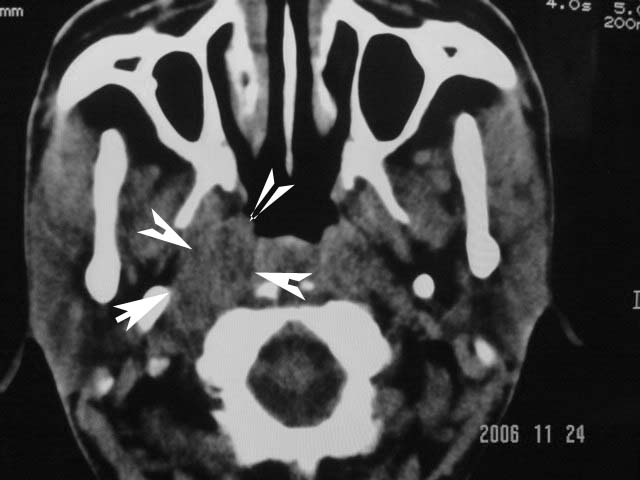

右侧鼻咽部软组织肿块,颅底骨质破坏,右侧颈部淋巴结肿大;诊断:鼻咽ca、右颈部淋巴结转移、颅底侵犯

右侧鼻口咽侧后壁不规则增厚,内可见密度不均匀性椭圆形软组织块影,边界欠清,咽旁间隙尚清.右颈部可见圆形软组织块影,鼻塞、耳鸣3个月,涕中带血2周,颈部可触及肿大淋巴结,考虑鼻咽癌,颈部淋巴转移.

右侧鼻咽后壁不规则增厚,内可见密度不均匀性椭圆形软组织块影,边界欠清,咽旁间隙尚清.右侧下方可见圆形软组织块影,双侧蝶窦呈均一高密度。

考虑:1、右侧鼻咽癌伴颈部淋巴结转移;

2、双侧蝶窦炎。

右侧鼻咽部软组织肿块,颅底骨质破坏,右侧颈部淋巴结肿大;诊断:右侧鼻咽ca伴右颈部淋巴结转移、颅底侵犯.

典型右侧鼻咽ca伴颈部淋巴结转移,中颅底骨侵蚀。

右侧鼻咽侧后壁不规则增厚,咽隐窝变钝,咽旁间隙变狭窄,见组织结节影[哨兵征],蝶骨似破坏,蝶窦内充塞软组织影,翼内外肌上分间隙模糊,右颈后三角区淋巴结肿大,右侧乳突增高气房消失。考虑鼻咽癌伴蝶窦侵犯及淋巴结转移,右侧浆液性中耳炎。其他恶性病变待排。